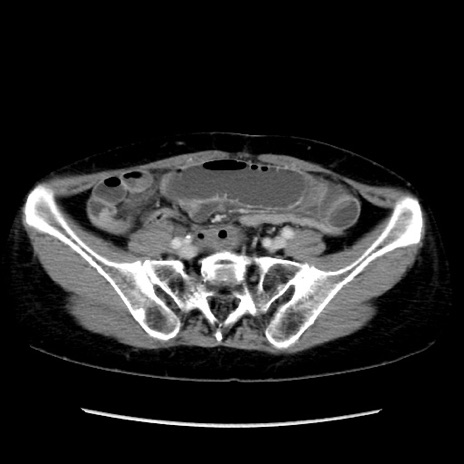

冠状断像

【症例】40歳代 女性

【主訴】上腹部痛、嘔気・嘔吐

【現病歴】約9時間前頃から急に上腹部痛、嘔気、嘔吐が出現。改善しないため救急要請。

【既往歴】子宮頚癌(広汎子宮全摘術、放射線療法)、腸閉塞

【身体所見】腹部:平坦、軟、腸雑音亢進、上腹部を中心に腹部全体に圧痛あり。

【データ】WBC 8400、CRP 0.03